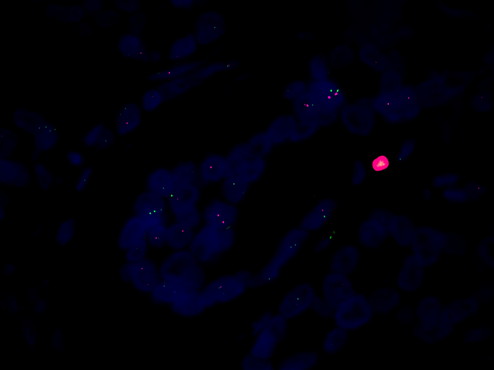

熒光顯微鏡觀察 HER-2:癌癥早篩的關(guān)鍵指標

FISH熒光原位雜交是一種先進的顯微鏡技術(shù),可以用于檢測 HER-2 的表達水平。在癌癥早篩中,熒光顯微鏡MF43-N可以用于對熒光染色的細胞進行觀察,然后通過觀察細胞中不同信號點的數(shù)量和分布來檢測 HER-2 的表達水平。這種技術(shù)可以有效地檢測出 HER-2 過度表達的細胞,為癌癥的早期診斷提供重要依據(jù)。

總結(jié)起來,熒光顯微鏡MF43-N結(jié)合FISH熒光原位雜交技術(shù)觀察 HER-2,是癌癥早篩中的有效技術(shù)。通過使用這種技術(shù),可以有效地檢測出癌癥的早期跡象,從而提高患者的生存率。